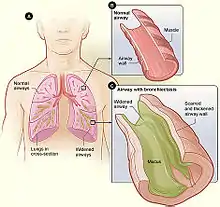

| Figure A shows a cross-section of the lungs with normal airways and widened airways. Figure B shows a cross-section of a normal airway. Figure C shows a cross-section of an airway with bronchiectasis. | |

Bronchiectasis is a disease in which there is permanent enlargement of parts of the airways of the lung.[5] Symptoms typically include a chronic cough with mucus production.[3] Other symptoms include shortness of breath, coughing up blood, and chest pain.[2] Wheezing and nail clubbing may also occur.[2] Those with the disease often get lung infections.[8]